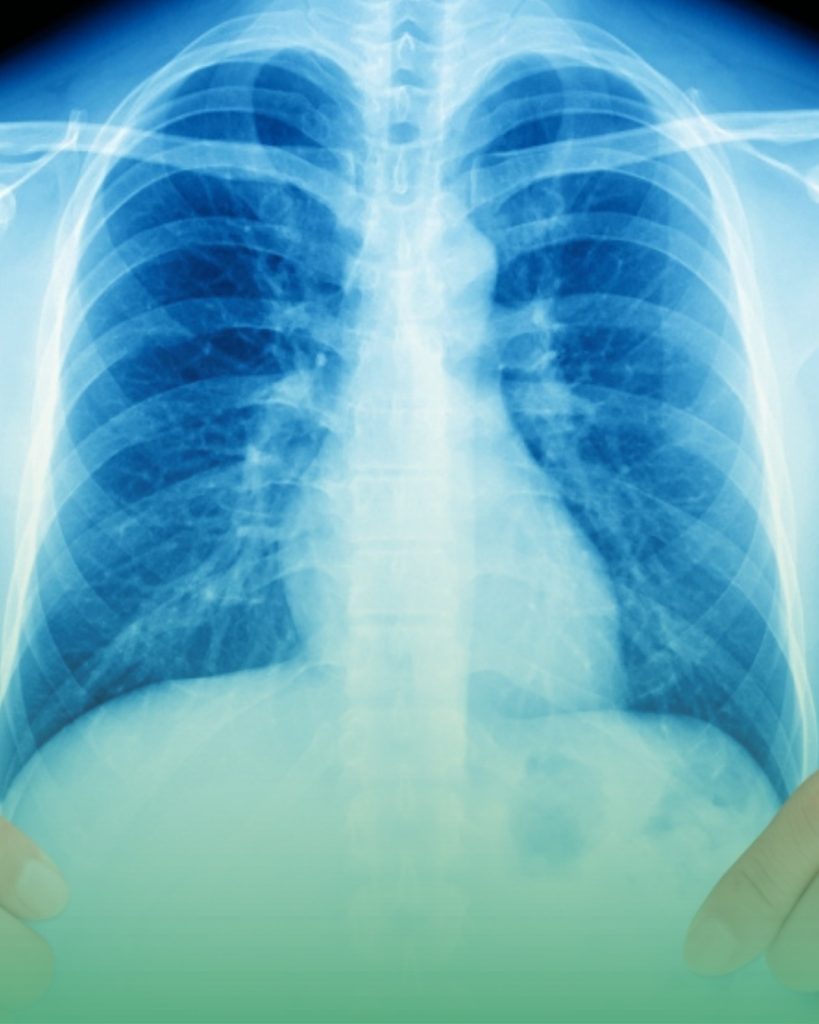

La radiologie générale (ou radiographie conventionnelle) est la technique d’imagerie médicale la plus ancienne et la plus couramment utilisée. Elle repose sur l’utilisation de rayons X qui traversent le corps et produisent des images des structures internes sur un détecteur numérique.

Au Centre de Radiologie Ibn Rochd, nous disposons d’un système de radiologie numérique directe (DR) de dernière génération qui permet d’obtenir des images de haute qualité avec une dose d’irradiation considérablement réduite par rapport aux anciens systèmes analogiques. Les résultats sont disponibles rapidement, permettant une prise en charge thérapeutique sans délai.